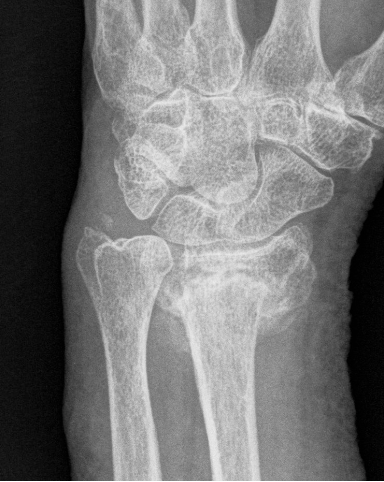

Corrective osteotomy of distal radius malunion

Corrective osteotomy of dorsally malunited fractures of the distal radius via the extended FCR approach DOI:10.1016/S0363-5023(03)80303-9 Cite this article: Orbay, Jorge & Indriago, Igor & Badia, Alejandro & Khouri, Roger & González, Eduardo & Fernandez, Diego. (2003). Corrective osteotomy of dorsally mai-united fractures of the distal radius via the extended FCR approach. Journal of Hand Surgery-american… [Read More]